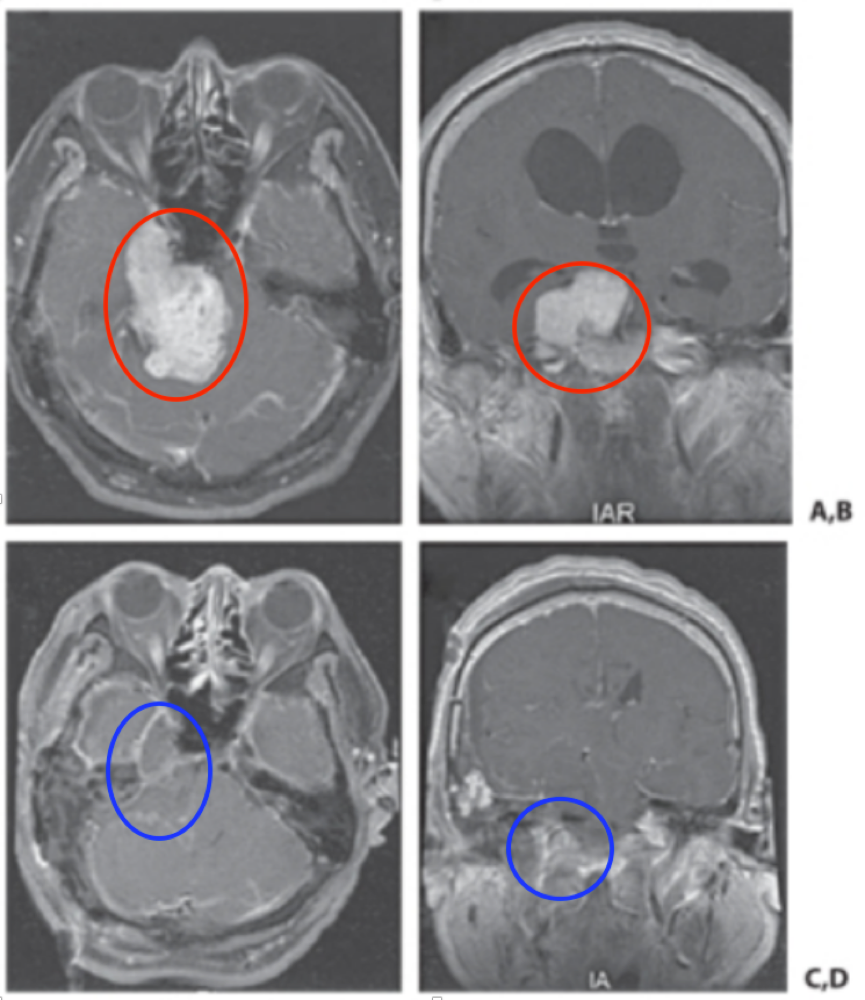

术前情况:一名54岁男士因越来越严重的走路不稳、突发眩晕发病,后就医发现脑干旁长了一个巨大的三叉神经鞘瘤,术前MRI肿瘤呈现为“哑铃型”。

后在William T.Couldwell教授及其手术团队的共同合作努力下,最终确定了以岩骨联合入路来实现肿瘤的完全切除,患者的三叉神经鞘瘤得以顺利全切,术后MRI显示完全切除。

(A、B)术前MRI显示一个巨大的三叉神经鞘瘤伴脑干压迫,(C,D)术后MRI显示完全切除。

术后情况:患者没有出现术中副作用,术后无明显并发症,3年后复查无复发。